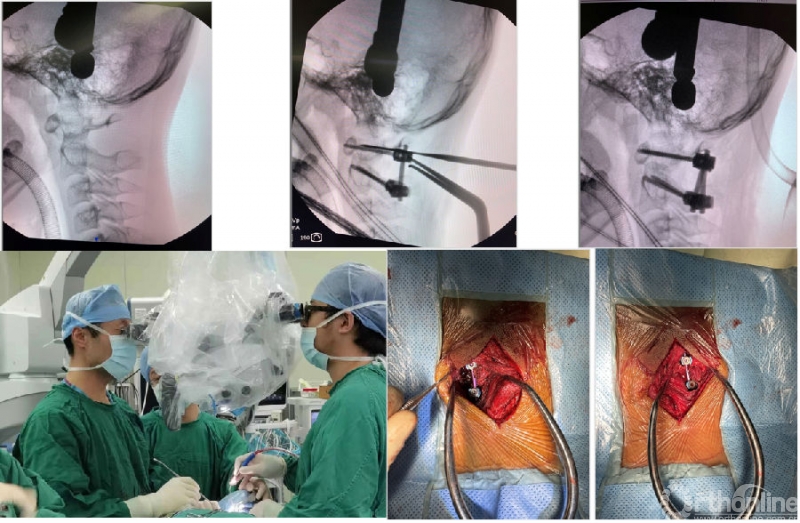

图4 男性55岁、诊断难复性寰枢椎脱位;经过单纯后路手术(侧块关节松解+植骨+钉棒复位固定术)获寰枢椎复位、融合。术后CT显示寰枢椎解剖复位、侧块关节间骨性融合。

常规的寰枢椎后路融合术需行颈后部肌肉的剥离。颈后部伸肌及枕下小肌群全部需要剥离,还需要髂骨取骨。术后颈后部轴性疼痛和取骨区的疼痛困扰着患者及术者。近年来,北医三院颅椎组开展了显微镜下经双侧肌肉间隙的寰枢椎融合术。保留了颈后伸肌张力带、同时从C2椎板和棘突根部取少许骨质,植入侧块间隙。